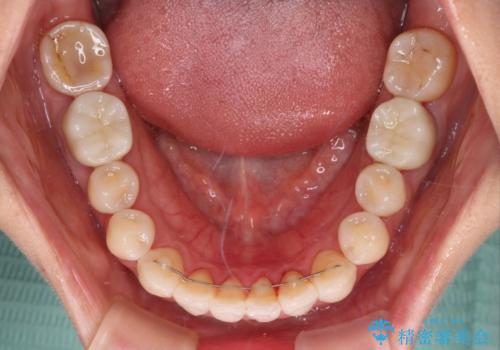

矯正治療後には期にある銀歯を全てセラミッククラウンなどで補綴治療することとしました。

インビザライン・ライトによる矯正治療であったので、時間をかけずに治療を終えることができました。

口を開ける度に目立っていた銀歯もセラミックで自然な口元の印象となりました。